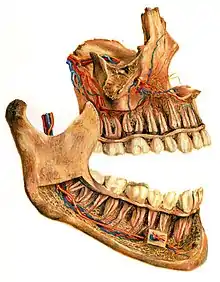

The alveolar process (/ælˈviːələr, ˌælviˈoʊlər, ˈælviələr/)[1] or alveolar bone is the thickened ridge of bone that contains the tooth sockets on the jaw bones (in humans, the maxilla and the mandible).[2] The structures are covered by gums as part of the oral cavity.

![]() Human jaws with anterior (frontal) portion of alveolar processes cut away towards right | |

On the maxilla, the alveolar process is a ridge on the inferior surface, making up the thickest part of the bone. On the mandible it is a ridge on the superior surface. The structures hold the teeth and are encased by gums as part of the oral cavity.[11] Either alveolar process comprises cells, nerves, blood vessels, lymphatic vessels, and periosteum.[8] The alveolar crest terminates uniformly at about the neck of the teeth (within about 1 to 2 mm in a healthy specimen).[12][13]

The alveolar process proper encases the tooth sockets, and contains a lining of compact bone around the roots of the teeth, called the lamina dura.[8] This is attached by the periodontal ligament (PDL) to the root cementum.[8] Although the alveolar process is composed of compact bone, it may be called the cribriform plate because it contains numerous holes where Volkmann's canals pass from the alveolar bone into the PDL. The alveolar bone proper is also called bundle bone because Sharpey's fibres, part of the PDL, are inserted there. Sharpey's fibres in alveolar bone proper are inserted at a right angle (just as with the cemental surface); they are fewer in number, but thicker in diameter than those found in cementum.[8]

The supporting alveolar bone consists of both cortical (compact) bone and trabecular bone. The cortical bone consists of plates on the facial and lingual surfaces of the alveolar bone. These cortical plates are usually about 1.5 to 3 mm thick over posterior teeth, but the thickness is highly variable around anterior teeth.[13] The trabecular bone consists of cancellous bone that is located between the alveolar bone proper and the cortical plates.[14]